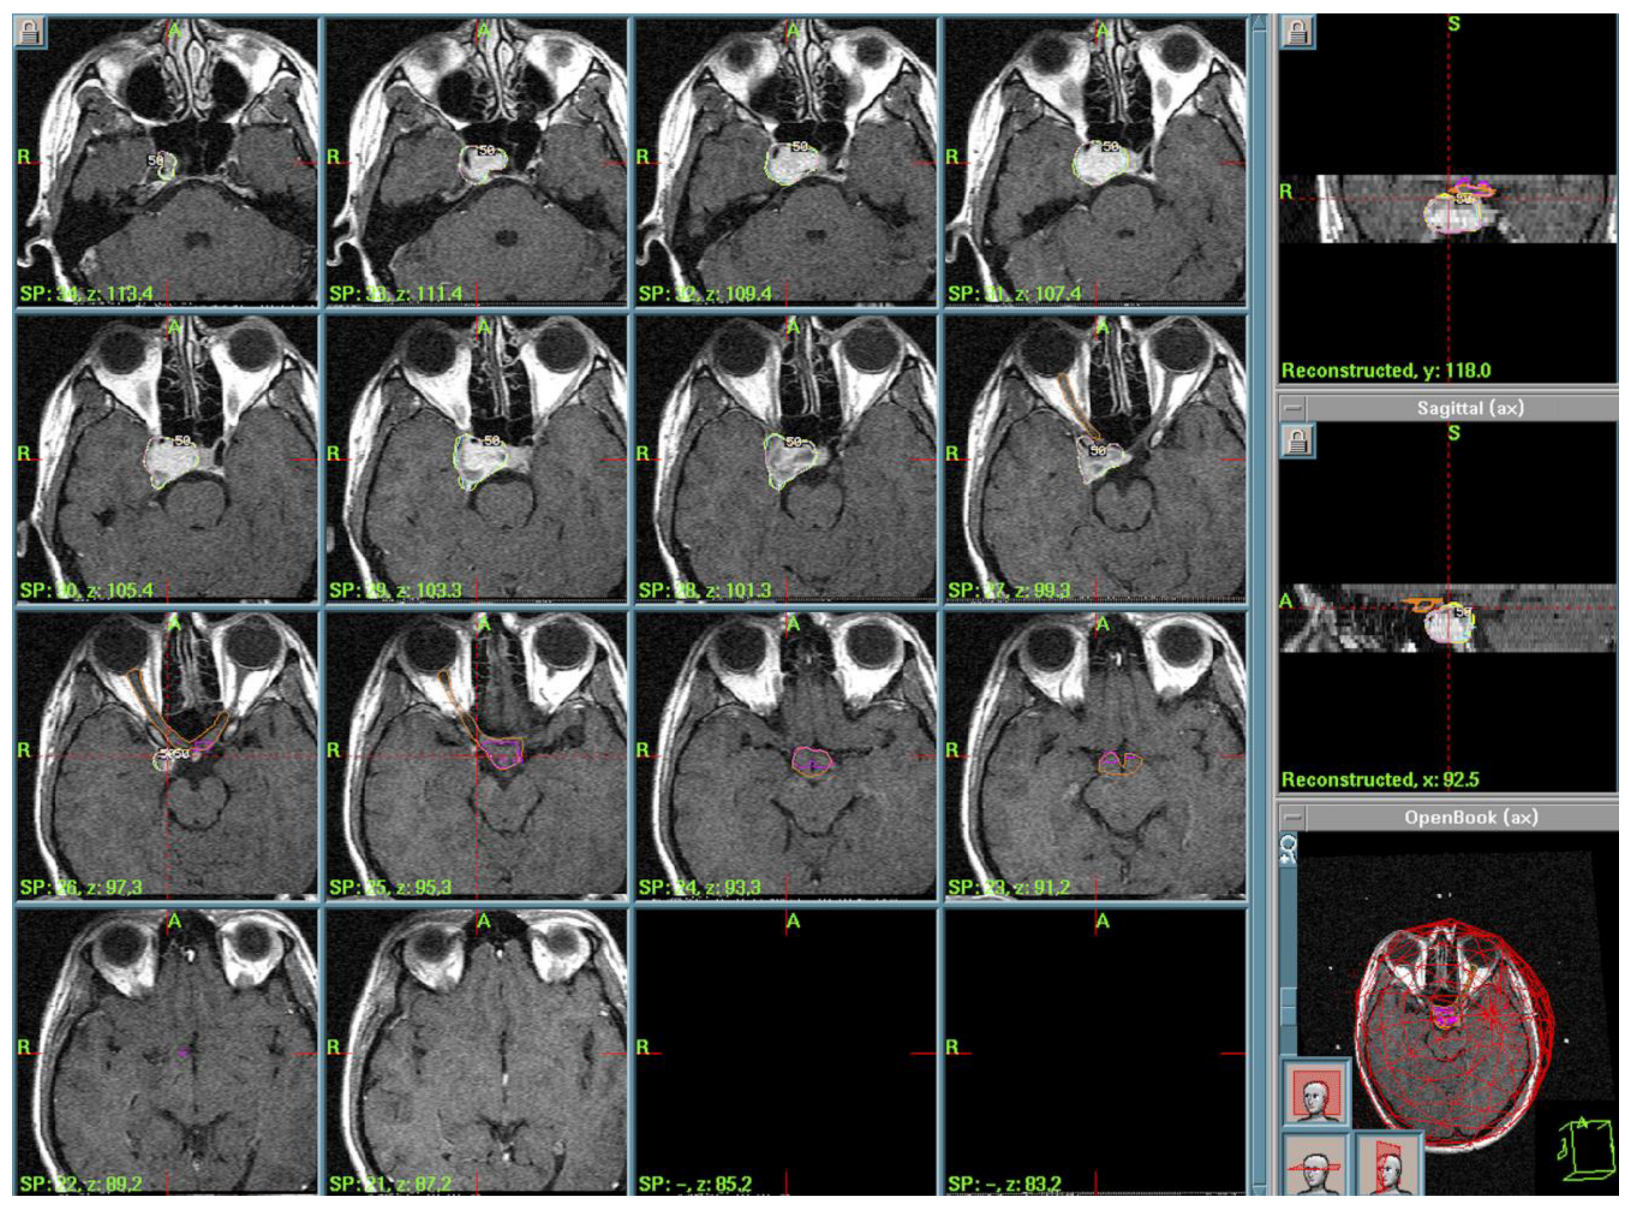

3.4. Ossifying Fibroma (OF) of the Ethmoid Sinus

| 7. | Ossifying Fibroma | PI of 50%, PD of 11 Gy, MD of 22 Gy | 2004–2016 |